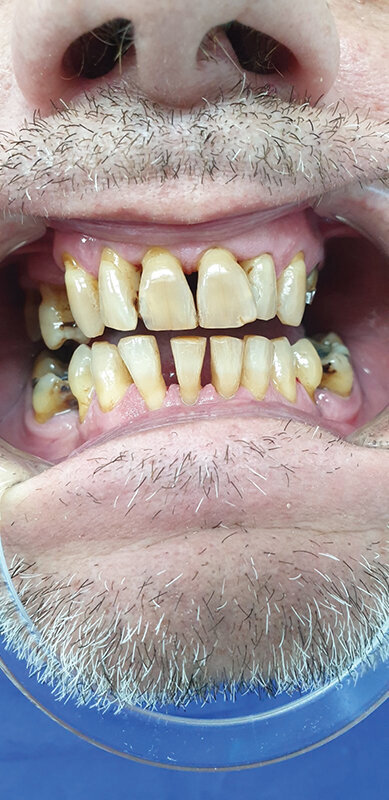

Pacijent muškog pola, starost 50 godina,višegodišnji pušač (dužina pušačkog staža preko 30 god., 30-40cig/dan; u daljem tekstu: Pacijent A) i pacijent muškog pola, starost 48 godina, višegodišnji pušač (30 god., oko 30cig/dan; u daljem tekstu: Pacijent B). Oba pacijenta se javljaju na redovnu kontrolu, poliranje zuba (uklanjanje pušačkih pigmentacija, zubnog kamenca i mekih naslaga). Žale se na brzo gomilanje estetski neprihvatljivih naslaga, otežanu oralnu higijenu, prebojavanje zuba, neprijatan zadah iz usta, suvoću usta, smanjen osećaj ukusa i mirisa i žarenje jezika. Nezadovoljni su i kratkotrajnošću postignutih estetskih rezultata. Nakon pregleda i uvidom u stomatološki karton, utvrđeno je da je od prošle njihove posete stomatologu prošlo svega 4 meseca.

Pacijent A pušač pri prijemu. Jasno se uočavaju naslage u vidu estetski neprihvatljivih pušačkih pigmentacija na svim površinama zuba. Nizak nivo oralne higijene ogleda se u nalazu zubnog kamenca i visokom Plak indexu. Jasno su uočljive pušačke melanoze vidljivog dela desni kao i suvoća i beličaste promene obraznog dela sluzokože. Obložen jezik takođe je karakterističan nalaz višegodišnjeg pušača (Sl. 1.0).

Pacijent B pušač pri prijemu. Estetski neprihvatljive pušačke pigmentacije na svim površinama zuba, naročito onim u estetskoj zoni, direktno izloženim glavnoj struji duvanskog dima. Zubni kamenac i meke naslage ukazuju na nizak nivo oralne higijene. Uočava se i prebojenost kompozitnih aproksimalnih plombi gornjih prednjih zuba. Slabije izražene melanogene pigmentacije desni. Jezik pacijenta takođe je obložen (Sl. 2.0).